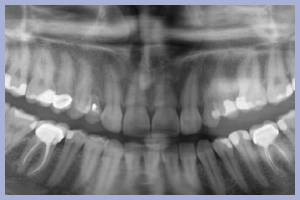

L’esame clinico iniziale (Figg. 1, 2) metteva in evidenza una buona situazione dento-parodontale generale; l’igiene orale e la collaborazione da parte della paziente, fortemente motivata alla soluzione del problema, erano ottime. L’esame radiologico ortopanoramico iniziale (Fig. 3) mostrava una buona quantità di osso apicalmente alle radici degli elementi decidui che apparivano sottili e parzialmente riassorbite. Il progetto terapeutico prevedeva un posizionamento implantare post-estrattivo immediato associato a carico immediato non funzionale tramite l’utilizzo di monconi temporanei e corone in resina precedentemente allestite, da ribasare in bocca dopo la preparazione dei monconi.

- Fig. 3 – Ortopantomografia iniziale